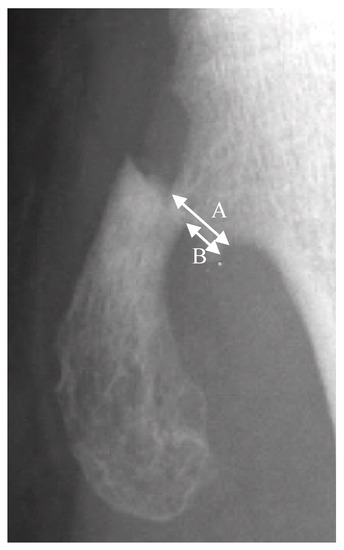

The fractures of the osteochondromas were divided into two types: displacement and non-displacement. In the present study, displacement was defined as a gap widening of more than 1 mm between fragments, or translation of more than 50% of the distal fragment in relation to the proximal fragment, either by anteroposterior, lateral, or oblique radiographic views of the knee joint (Figure 1). There were 12 patients in the displacement group and 11 patients in the non-displacement group (Figure 2).

Figure 1.

A is the width of the proximal fragment of the fractured osteochondroma. B is the displaced distance of the distal fragment in relation to the proximal fragment. Translation is defined by the equation of B/A × 100%.